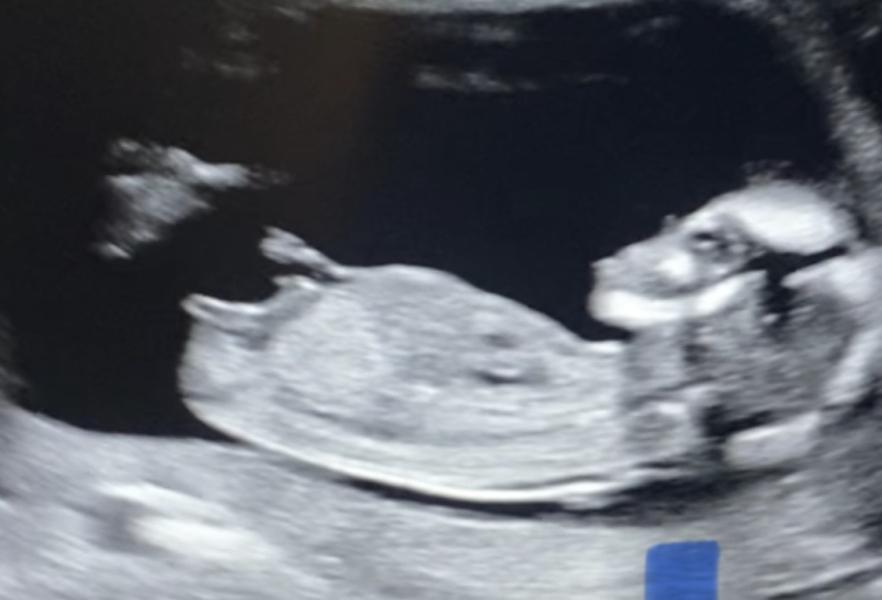

post image 3

Девочки, кто разбирается, тут уже виден пол ребенка?

Теперь знаю, сегодня родила , большинство были правы-девочка!

Мне кажется тоже девочка половой бугорок вниз

На девочку похоже

Если посмотреть как выглядит половой бугорок у мальчиков, то он вверх

Но еще зависит от ракурса снимка

Тут вообще ничего не увидеть , закрылся ножками